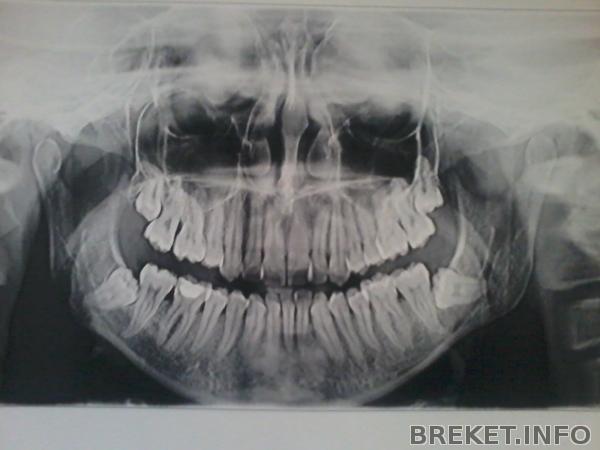

Привет всем!Очень часто поднимается тема удаления ретинированных восьмерок.И мне тоже предстоит с этим столкнутся :smile33:Удалять восмерки орт сказала на нч. Я посмотрела на свой снимок и очень расстроилась!Получается,что нижние восьмерки на нерве обе лежат.Еще на консультацию к хирургу не ходила,может у кого похожая ситуация была?Если задеть нерв,потом что,всю жизнь с перекошенным лицом ходить?

2013-07-15_10.58.47.jpg